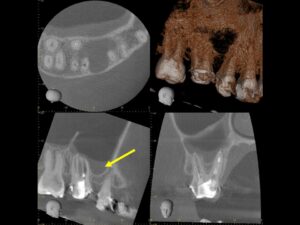

初診時CT画像。上顎洞に当該歯の部位に一致するX線不透過性の亢進を認める。繰り返し根管治療を行ったためか、根尖部は破壊されて太く開いている。また、湾曲した根管を何度も治療を行ったため、根尖部のパーフォレーションを認めた。